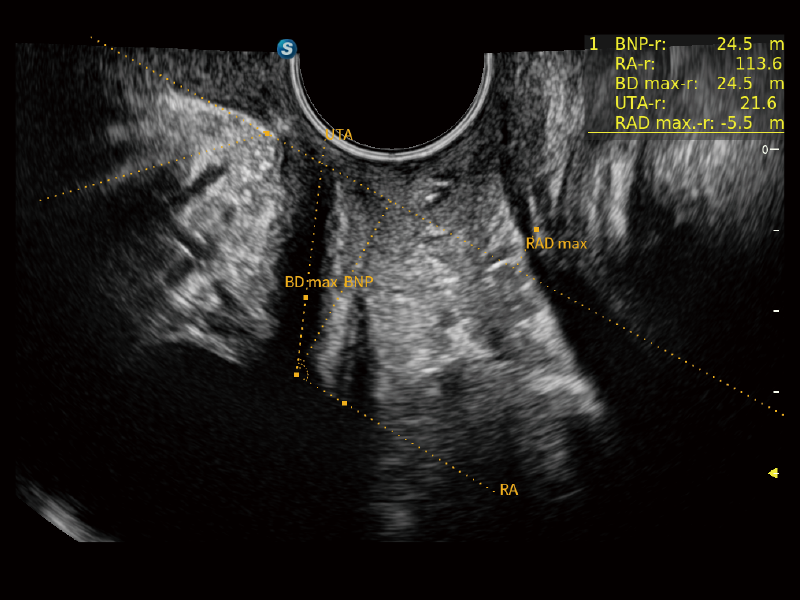

独有场成像发射技术

自适应聚合重建技术

作为开立医疗全新打造的超高端旗舰超声产品,从探头抬起唤醒开启扫查到多维探头发射接收,通过先进的场成像发射、自适应聚合重建等技术,基于RF Data原始射频数据在图像生成、高端功能等方面实现突破,为妇产科、儿科提供全方位临床解决方案。